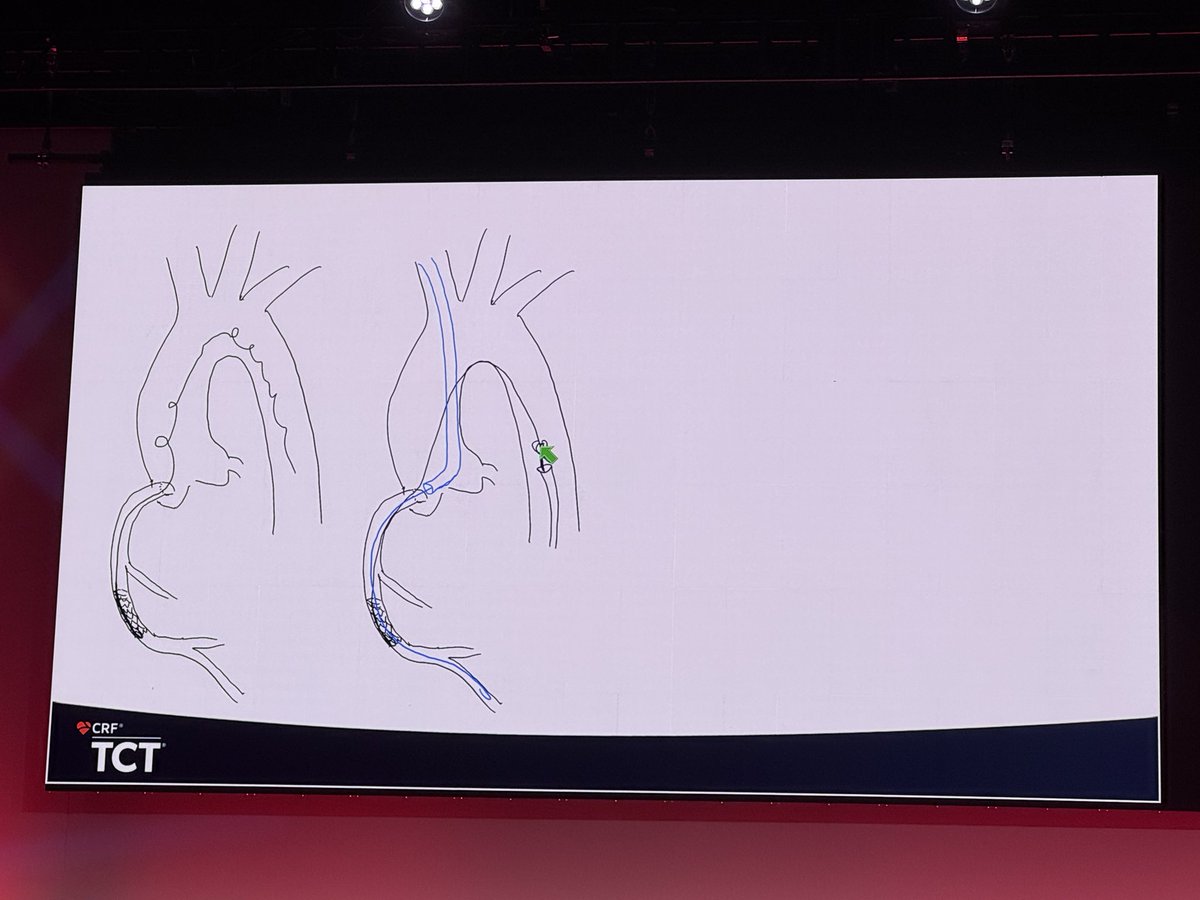

Lost MC tips and unraveled wire, cut with rota!!! #CardioX #CardioTwitter #CardioEd #CardioResearch @BurkhoffMd @djc795 @ColletCarlos @georgedangas @jgranadacrf @MartyBLeon @Drroxmehran @sahilparikhmd @PopmaJeffrey @triciarawh @mirvatalasnag @TCTConference @TCTMD @jedicath…

Lost MC tips and unraveled wire, cut with rota!!! #CardioX #CardioTwitter #CardioEd #CardioResearch @BurkhoffMd @djc795 @ColletCarlos @georgedangas @jgranadacrf @MartyBLeon @Drroxmehran @sahilparikhmd @PopmaJeffrey @triciarawh @mirvatalasnag @TCTConference @TCTMD @jedicath…